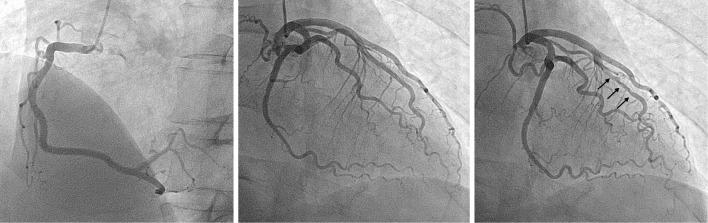

A 61-year-old man experienced chest oppression for 1 hour. He was positive for troponin T and underwent emergent coronary angiography (CAG), which did not reveal significant coronary stenosis. He was diagnosed with myocardial infarction with nonobstructive coronary arteries (MINOCA). We performed a spasm-provocation test, which revealed a focal spasm at the segment of the myocardial bridge. After receiving a calcium-channel blocker, he exhibited a good clinical course. Coronary spasm is considered an underlying cause of MINOCA; therefore, the presence of a myocardial bridge may help with the diagnosis.

一名61岁男性经历了1小时的胸部压迫感。他肌钙蛋白T呈阳性,接受了急诊冠状动脉造影(CAG),结果未显示明显的冠状动脉狭窄。他被诊断为非阻塞性冠状动脉心肌梗死(MINOCA)。我们进行了痉挛激发试验,结果显示心肌桥节段存在局灶性痉挛。在接受钙通道阻滞剂治疗后,他的临床病程良好。冠状动脉痉挛被认为是MINOCA的潜在病因;因此,心肌桥的存在可能有助于诊断。